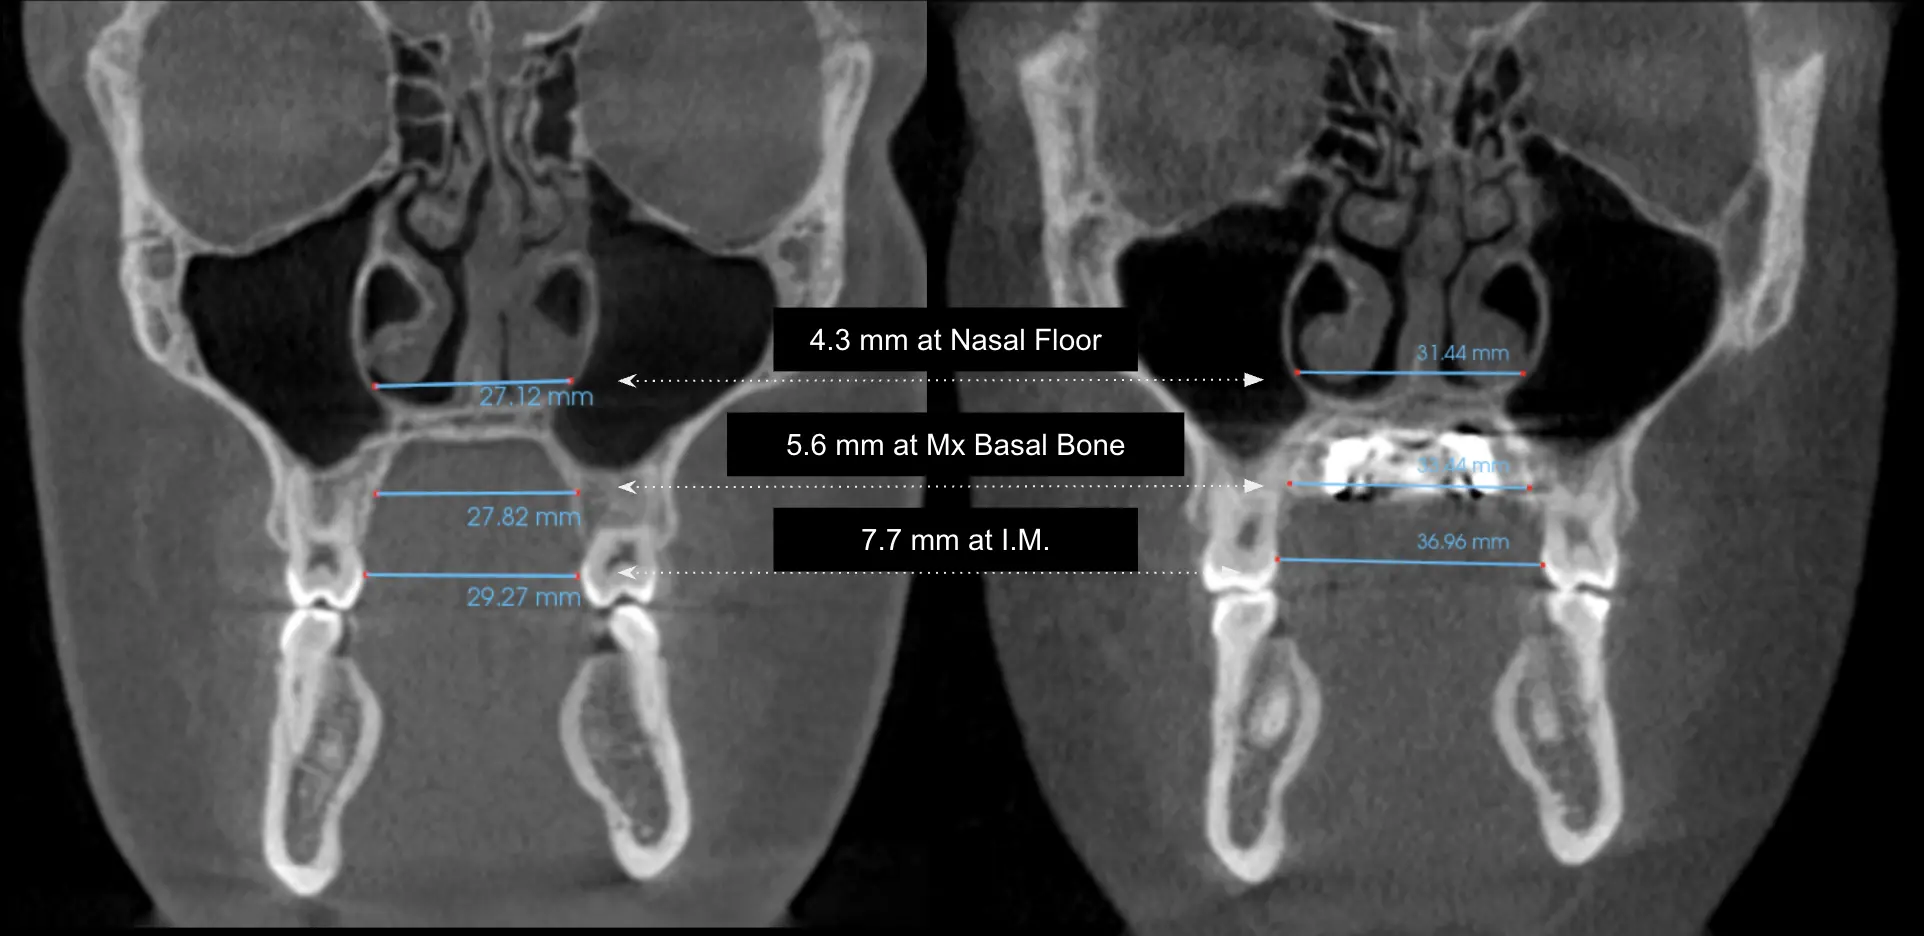

MARPE expansion progress over time